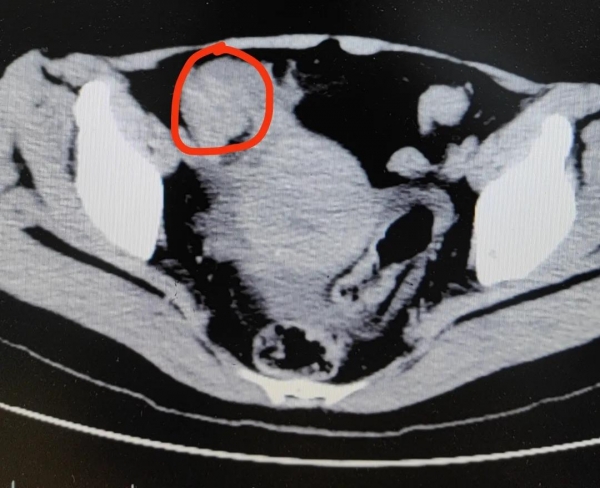

医生高度怀疑,冯女士发生了绞窄性肠梗阻。最后手术从肠子里切出一堆"石头",也就是俗称的"柿石症",最大的直径有4公分!

原来,柿子中含有较多的鞣酸和果胶,与虾、蟹、鱼、牛奶等高蛋白食物同食,因蛋白与鞣酸相遇,容易发生反应产生沉淀物--鞣酸蛋白,当胃里的胃酸较多的情况下,鞣酸蛋白和食物中的果胶、纤维素等,把食物残渣粘合在一起,在胃内形成胃柿石,造成胃部不适。